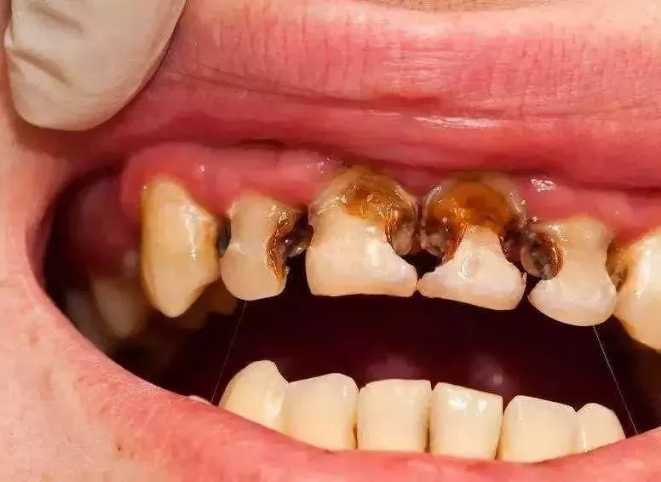

最近,一組照片讓幫幫看得觸目驚心!

小小年紀(jì),牙齒就能壞到這種程度?真是令人意想不到。據(jù)衛(wèi)計(jì)委2018年調(diào)查顯示:5歲兒童齲齒的比例竟然高達(dá)70%以上!

這么多娃的牙齒遭殃,歸根到底,還是家長認(rèn)為乳牙反正都是要替換的,乳牙齲病不必治療。但是,乳牙真的不重要么?